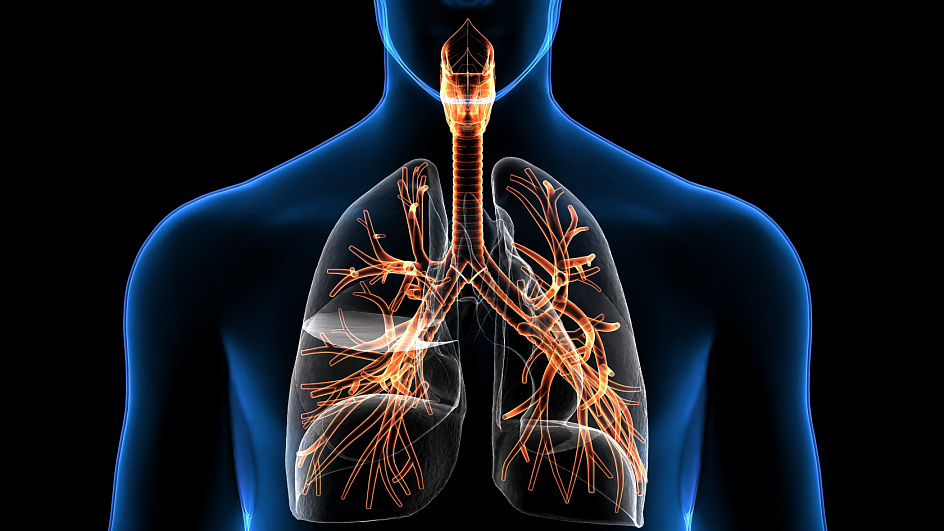

Дыхательная система

Для правильной жизнедеятельности человеку необходим кислород, который попадает в организм благодаря работе легких – основных органов дыхательной системы.

Функция дыхания в анатомии человека

Система дыхания человека отвечает за насыщение организма молекулами кислорода, а также выведение отработанного углекислого газа и токсических соединений. По сути, это последовательно соединённые между собой трубки и полости, которые сначала заполняются вдыхаемым воздухом, а потом изгоняют изнутри углекислый газ.

Верхние дыхательные пути представлены носовой полостью, носоглоткой и гортанью. Там воздух согревается до комфортной температуры, позволяя предотвратить переохлаждение нижних отделов дыхательного комплекса. Кроме того, слизь носа увлажняет слишком сухие потоки и обволакивает плотные мельчайшие частички, которые могут травмировать чувствительную слизистую.

Нижние дыхательные пути начинаются гортанью, в которой не только осуществляется функция дыхания, но и формируется голос. При колебании голосовых связок гортани возникает звуковая волна, однако трансформируется в членораздельную речь она только в ротовой полости, с помощью языка, губ и мягкого нёба.

Далее воздушный поток проникает в трахею — трубку из двух десятков хрящевых полуколец, которая прилегает к пищеводу и впоследствии распадается на 2 отдельных бронха. Затем бронхи, впадающие в ткани лёгких, ветвятся на меньшие по размеру бронхиолы и т. д., вплоть до образования бронхиального дерева. Сама же лёгочная ткань, состоящая из альвеол, отвечает за газообмен — всасывание кислорода из бронхов и последующую отдачу углекислоты.